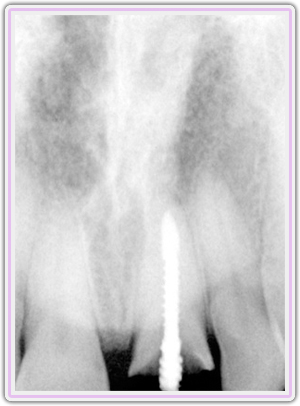

Pre-op X-Ray Showing The Fracture

X-Ray Showing The Custom Abutment In Place

Final X-Ray Showing Implant